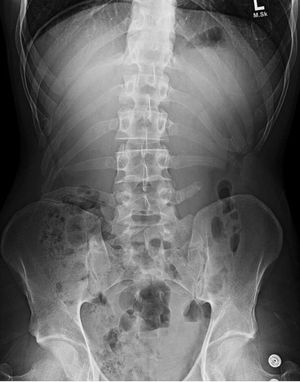

True, but I think the fact he has ribs all the way down his spine is pretty unusual.

As far as i know Scoliosis is not a medical emergency. The ribs however continue down to lumbat vertebrae after the thoracic.